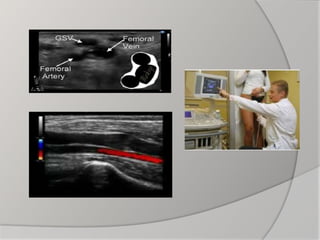

- Duplex ultrasound: The best; gives both anatomical

and functional diagnosis

- Others: e.g. CT venography and MRI rarely needed

 Duplex US is essential to identify

superficial, deep or perforator vein reflux

 General: - Assessthe general condition of the patient: e.g. CBC,liver and kidney function tests  Specific: - Hand-held Doppler - Duplex ultrasound: The best; gives both anatomical and functional diagnosis - Others: e.g. CT venography and MRI rarely needed